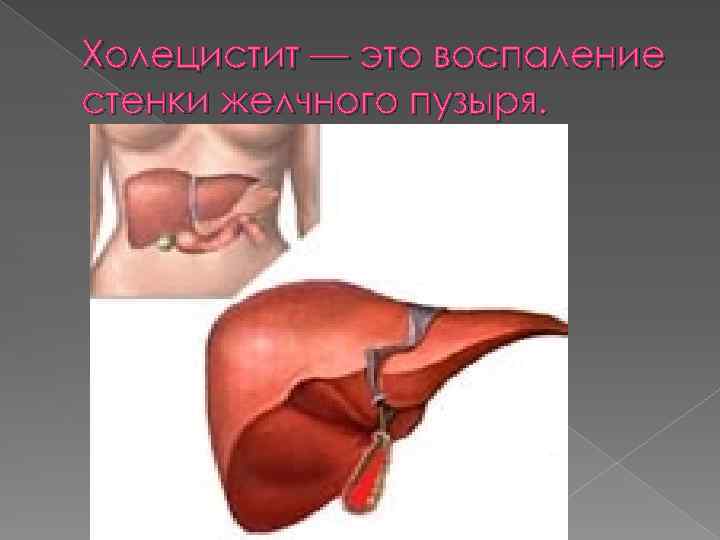

Холецистит — это воспаление стенки желчного пузыря.

Холецистит — это воспаление стенки желчного пузыря.

ЖЕЛЧЬ И ЖЕЛЧНЫЙ ПУЗЫРЬ Желчный пузырь расположен на нижней поверхности печени. Это полый орган в котором скапливается желчь. Основным действующим компонентом печени являются желчные кислоты.

ЖЕЛЧЬ И ЖЕЛЧНЫЙ ПУЗЫРЬ Желчный пузырь расположен на нижней поверхности печени. Это полый орган в котором скапливается желчь. Основным действующим компонентом печени являются желчные кислоты.